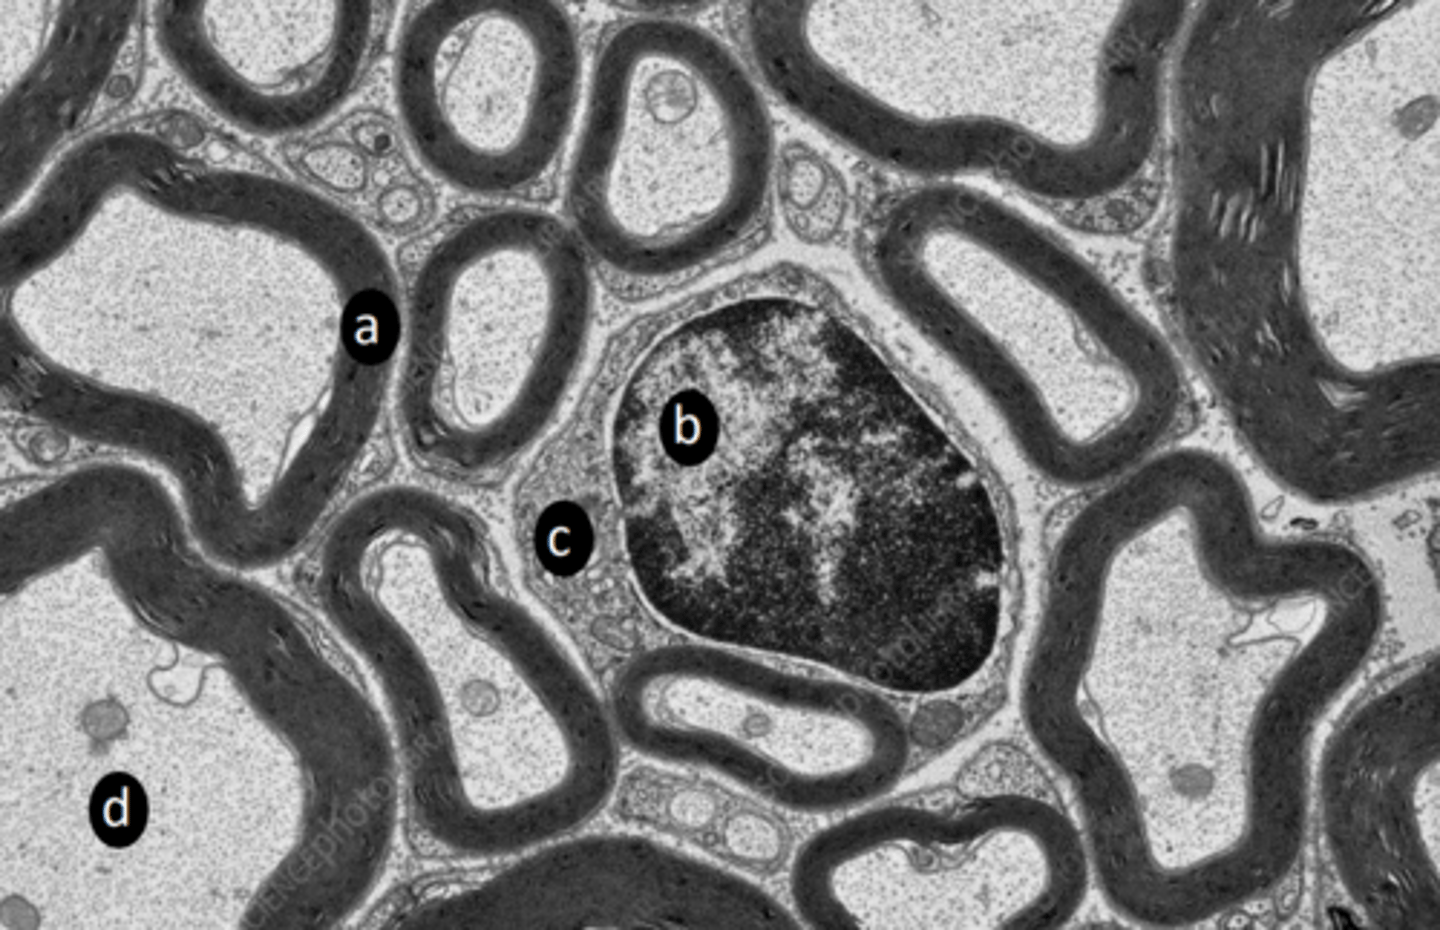

New cards

myelin sheath

a: structure

<p>a: structure</p>

9

schwann cell nucleus

b: structure

<p>b: structure</p>

10

schwann cell cytoplasm

c: structure

<p>c: structure</p>

11

microtubule, neurofilament, mitochondria

d: two structures present in labelled region

<p>d: two structures present in labelled region</p>